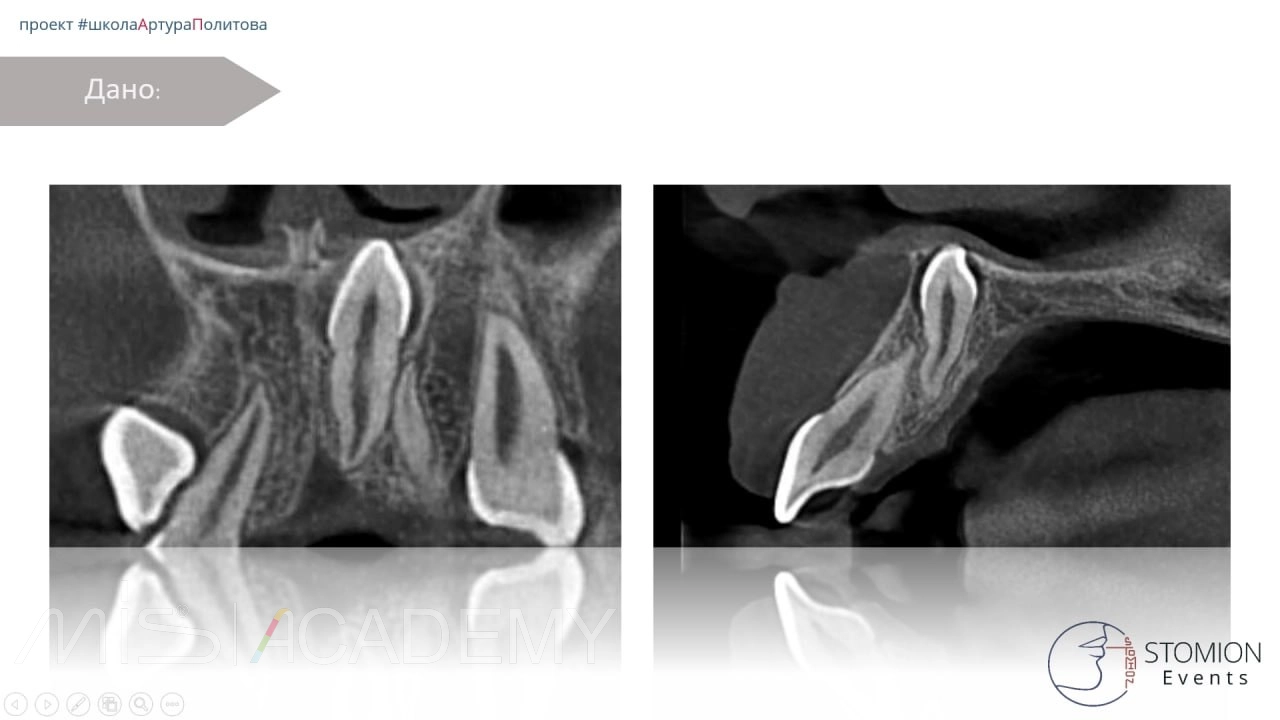

Пациентка направлена ортодонтом на удаление мезиоденса.

— Трепанация в области истонченного кортикала, чтобы не травмировать сосудистонервный пучок.

— Сегментация.

— Извлечение центральной части коронки, далее бугра, далее смещение зуба в просвет и сегментация по типу шинковки до полной экстракции.